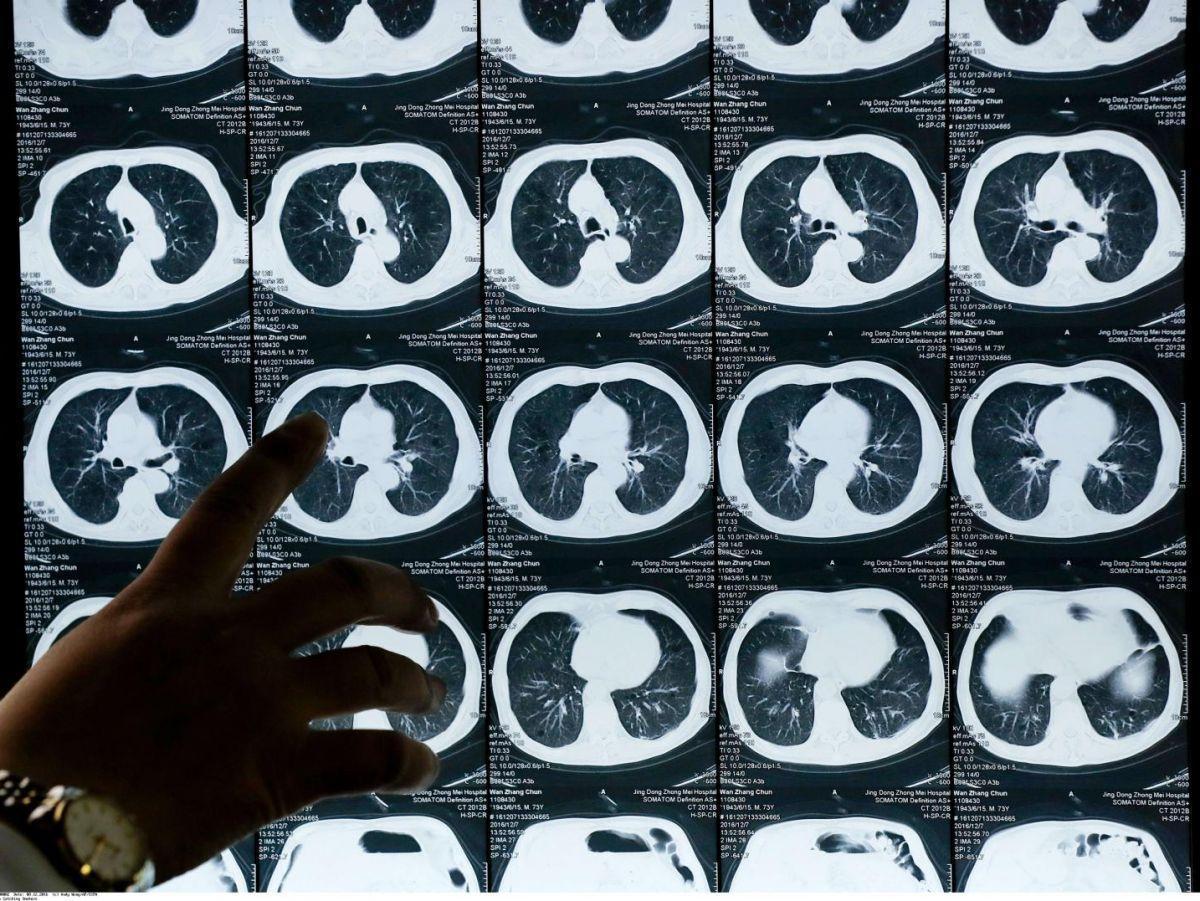

Un traitement pour les patients atteints de la forme la plus commune de cancer du poumon

Cette annonce orale a été de plus accompagnée par une publication simultanée dans le New England Journal of Medicine, ce qui vient évidemment renforcer l’importance de son résultat. Elle concerne les patients atteints d’un cancer dit “non à petites cellules”, la forme la plus commune de ce type de cancer, présentant un type particulier de mutation, dit de type Egfr, soit environ 10 % à 25 % des patients aux États-Unis et en Europe, 30 % à 40 % en Asie.

Une fois opérés car repérés à un stade précoce, les patients inclus dans l’essai Adaura (environ 700 malades répartis dans une vingtaine de pays) ont été divisés en deux groupes.